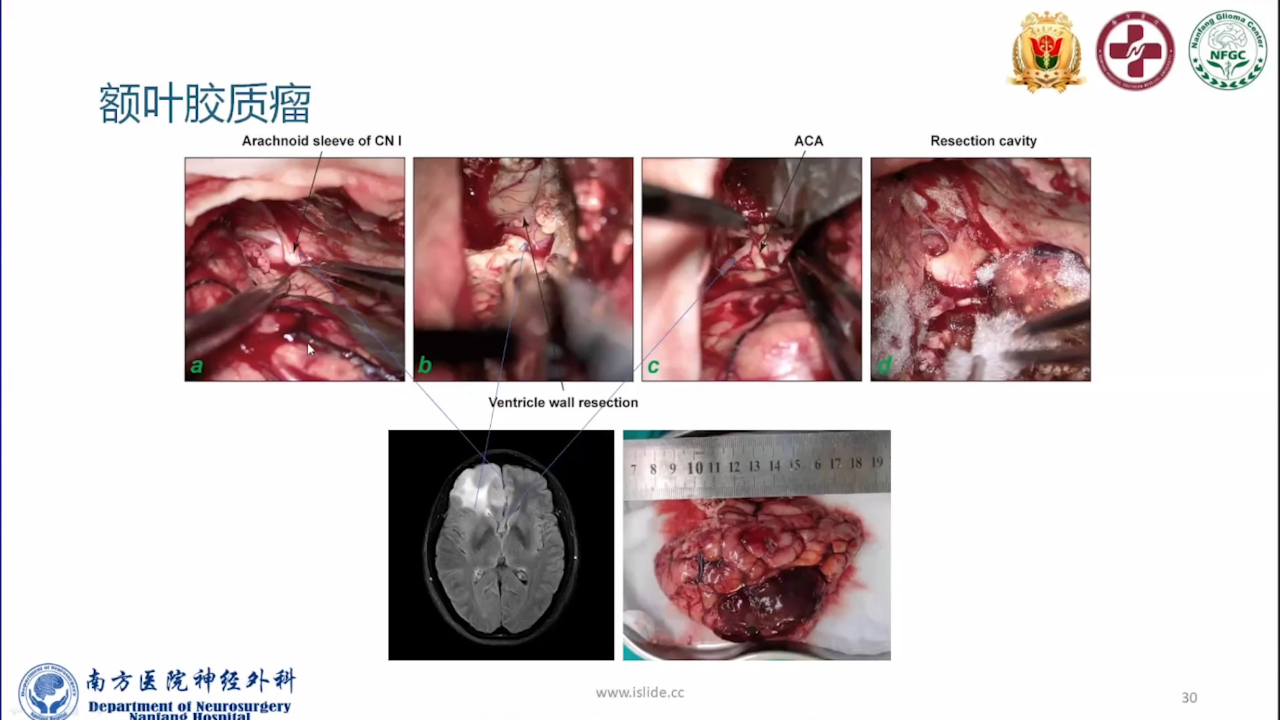

巨大的脑胶质瘤往往破坏皮层功能,推挤白质纤维束,包裹重要供血动脉,正常解剖结构移位。手术切除病变可以挽救患者生命。如果术中确保重要动脉不损伤,并在术前纤维束成像指导下按照解剖结构标志尽可能保留神经纤维束,患者将在获得辅助治疗机会的同时,神经功能也得以逐步恢复,更有利于脑胶质瘤的预后。